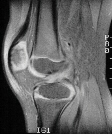

This patient is an 8 year old white male with no significant past medical

history, who slammed his knee in a car door 5 weeks prior to presentation.

He complains of right knee pain, swelling, and decreased range of motion.

The patient denies locking of the knee, but gives a questionable history

of "giving way" of the knee. On physical examination, the patient

has a small effusion. There is no medial or lateral joint line tenderness.

There is no tenderness around the collateral ligaments. Range of motion

is 30-90 degrees. There is no instability to varus or valgus stressing

at 0 degrees and 30 degrees. MacMurray test is negative. Lachman test shows

a slight increase in laxity compared to the contralateral side, but with

an endpoint. Anterior drawer test also shows a good endpoint. Posterior

drawer test is negative. KT-1000 testing was equal on both sides. The patient

was sent for physical therapy and an MRI to rule out ligament or meniscal

injury. The MRI was read by radiologist as anterior cruciate ligament tear

and small medial meniscal tear (images above).